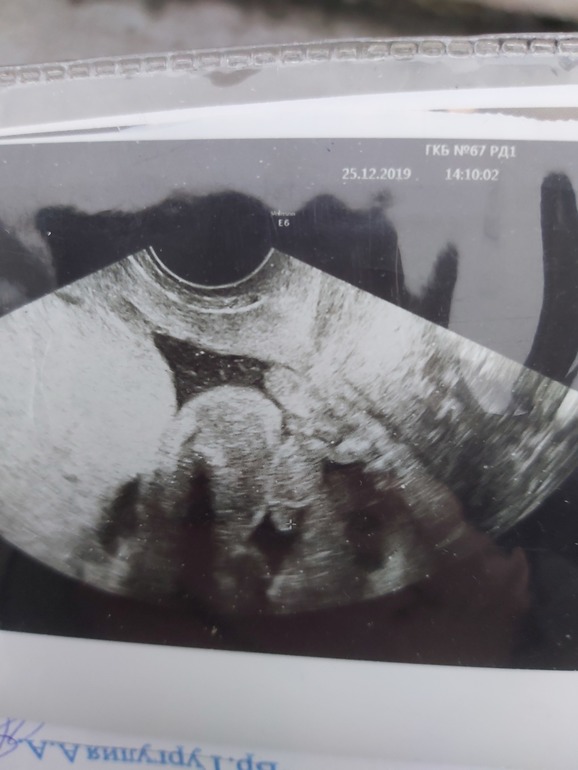

Девчченки, вот и пролетело 20 недель, сходила на узи, предположили девочку, а ваше мнение, или взгляд?))))

Сходила я на скрининг, и у нас будет сыночек!!!!!!)))))

у моего мужчины вот такое хозяйство 😄